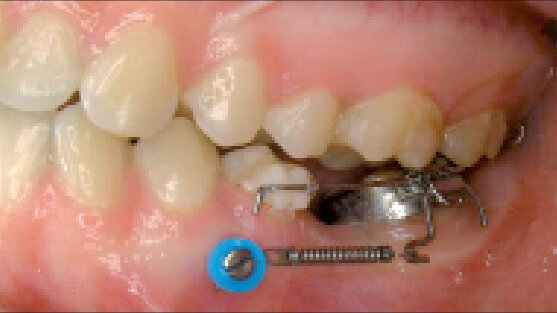

Aby pacient pociťoval co nejmenší nepohodlí, měla by být hlava šroubu velice malá a kompaktní. Musí nicméně být dostatečně velká, aby na ni bylo možné bezpečně upevnit spojovací prvky (Obr. 9a, 9b).

Transgingivální část

Transgingivální část, rovněž zvaná gingivální krček, je nejzranitelnější částí implantátu nebo miniimplantátu. Perforace gingivy může být potenciálním místem vstupu mikroorganizmů představujících riziko vzniku zánětu v okolí miniimplantátu nebo v okolní sliznici – jedné z hlavních příčin předčasné ztráty miniimplantátů.35–36

Bezprostředně po zavedení by měla sliznice těsně přiléhat ke šroubu, pro zajištění těsnění celé oblasti.37 Nejvýhodnější tvar transgingiválního krčku je konický, protože vytváří přirozený uzávěr bez tlakové zóny. To, čímž ztěžuje mikroorganizmům průnik, a předchází infekci. Konický tvar také uzavírá ránu perforace tak, jako korkový špunt uzavírá lahev, čímž se snižuje krvácení.